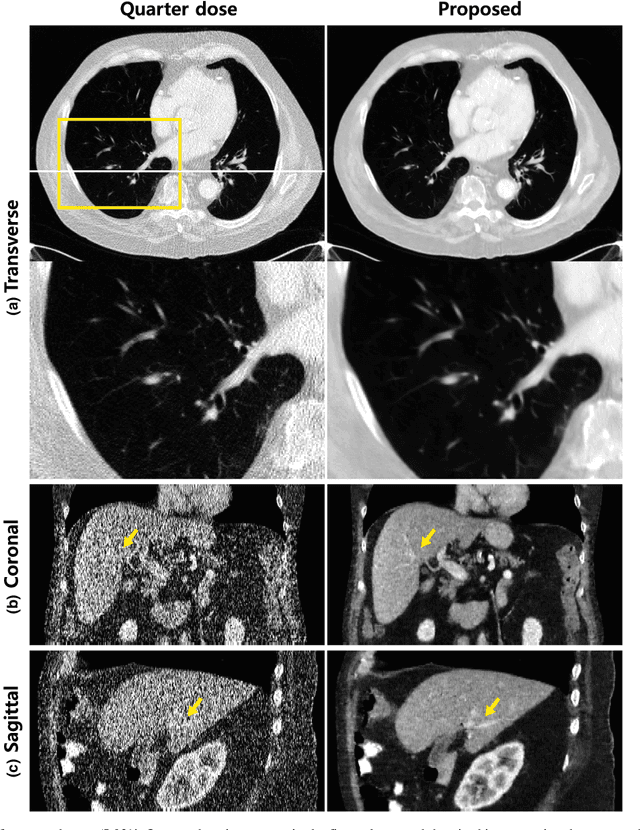

Abstract:In coronary CT angiography, a series of CT images are taken at different levels of radiation dose during the examination. Although this reduces the total radiation dose, the image quality during the low-dose phases is significantly degraded. To address this problem, here we propose a novel semi-supervised learning technique that can remove the noises of the CT images obtained in the low-dose phases by learning from the CT images in the routine dose phases. Although a supervised learning approach is not possible due to the differences in the underlying heart structure in two phases, the images in the two phases are closely related so that we propose a cycle-consistent adversarial denoising network to learn the non-degenerate mapping between the low and high dose cardiac phases. Experimental results showed that the proposed method effectively reduces the noise in the low-dose CT image while the preserving detailed texture and edge information. Moreover, thanks to the cyclic consistency and identity loss, the proposed network does not create any artificial features that are not present in the input images. Visual grading and quality evaluation also confirm that the proposed method provides significant improvement in diagnostic quality.